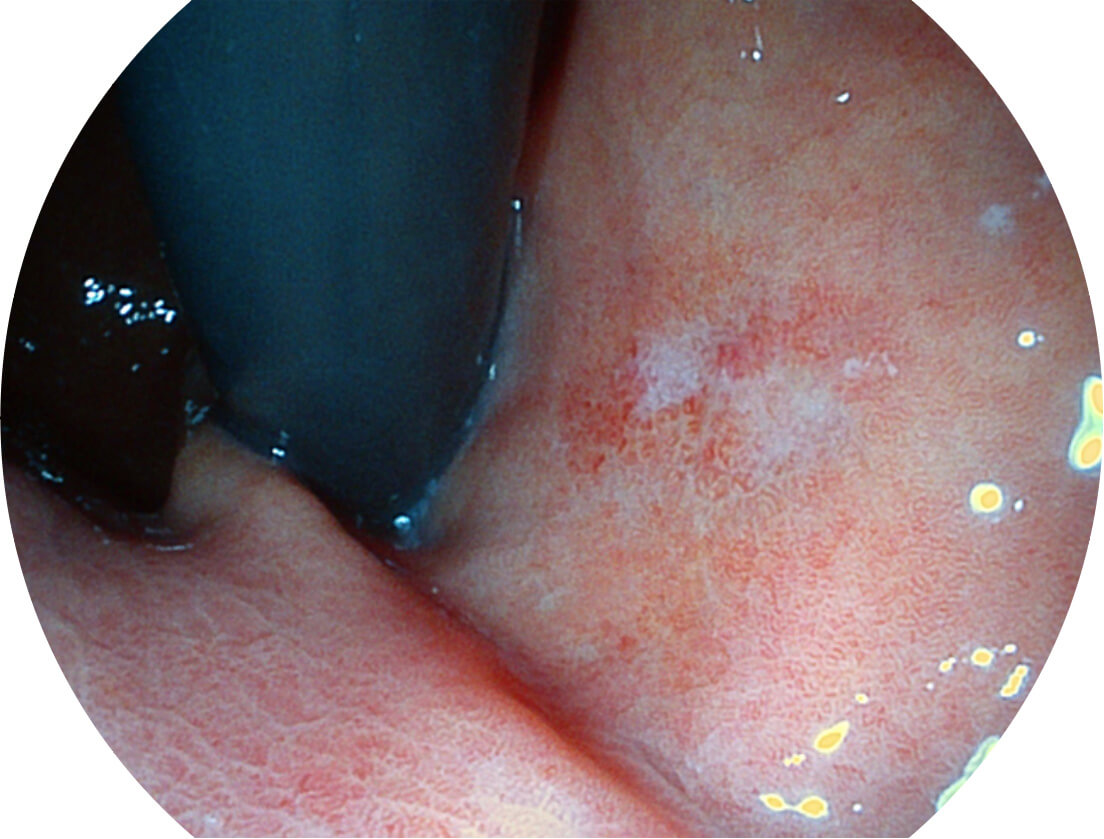

Spectral Focused lmaging, SFI

图像具有高亮度、高黏膜血管颜色对比度的特点,且不改变粘液、食物残渣、粪便的基本颜色,可在中远景下进行观察,助力消化道早期疾病的诊断。

SFI图像

白光图像